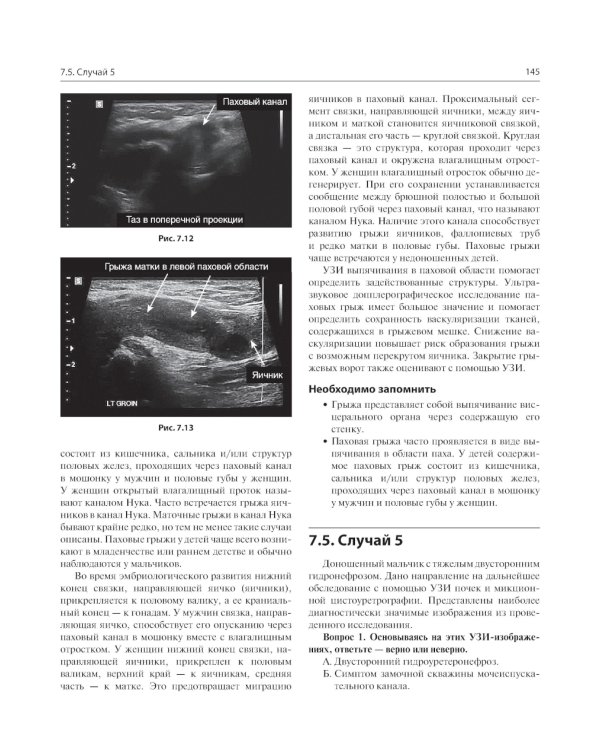

В книге рассмотрены сложные клинические радиологические случаи, охватывающие патологию центральной нервной системы, дыхательной и сердечно-сосудистой систем, желудочно-кишечного тракта, мочеполовой системы и опорно-двигательного аппарата в педиатрической практике. Случаи представлены с соответствующей историей болезни и подходящими изображениями исследований, за которыми следует обсуждение рентгенологических заключений при использовании различных методов лучевой диагностики. Также, в конце описания каждого случая выделены ключевые моменты, которые необходимо запомнить. Книга объединяет опыт врачей-рентгенологов и клинических ординаторов и представляет актуальную учебную информацию, способствующую улучшению качества оказания медицинской помощи. Издание предназначено врачам лучевой диагностики, врачам-радиологам и врачам клинической практики, работающим в педиатрических клиниках и детских больницах.